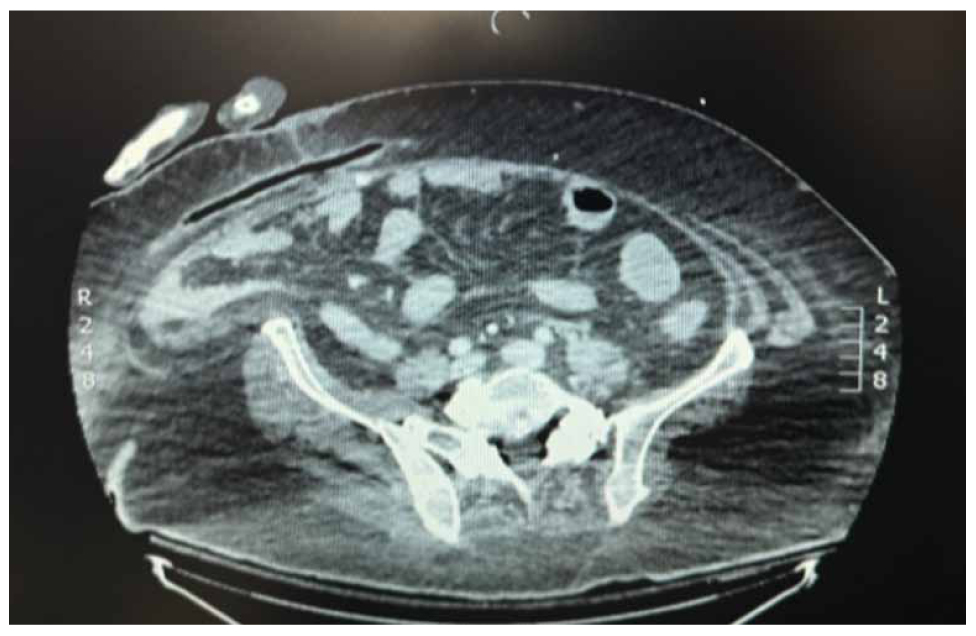

A 55-year-old super-super obese male with a BMI of 62 kg/m² presented to the emergency department with five days of abdominal pain and vomiting of intestinal contents. Upon presentation, he was haemodynamically unstable, with a systolic blood pressure of 85mmHg and 130 bpm. The patient had no history of prior abdominal surgeries. Clinical examination revealed a distended abdomen with tympanicity, hyperactive bowel sounds, tenderness, and rebound tenderness. Laboratory tests showed leukocytosis and elevated C-reactive protein (CRP). Imaging findings included an upright abdominal X-ray showing air-fluid levels in small and large intestines and a CT scan identifying a large midline and right lateral abdominal wall hernia containing small and large bowel, including the ileocecal valve (Figure 1).

Figure 1. Preoperative CT scan showing a large midline and right lateral abdominal wall hernia containing small and large bowel, including the ileocecal valve.